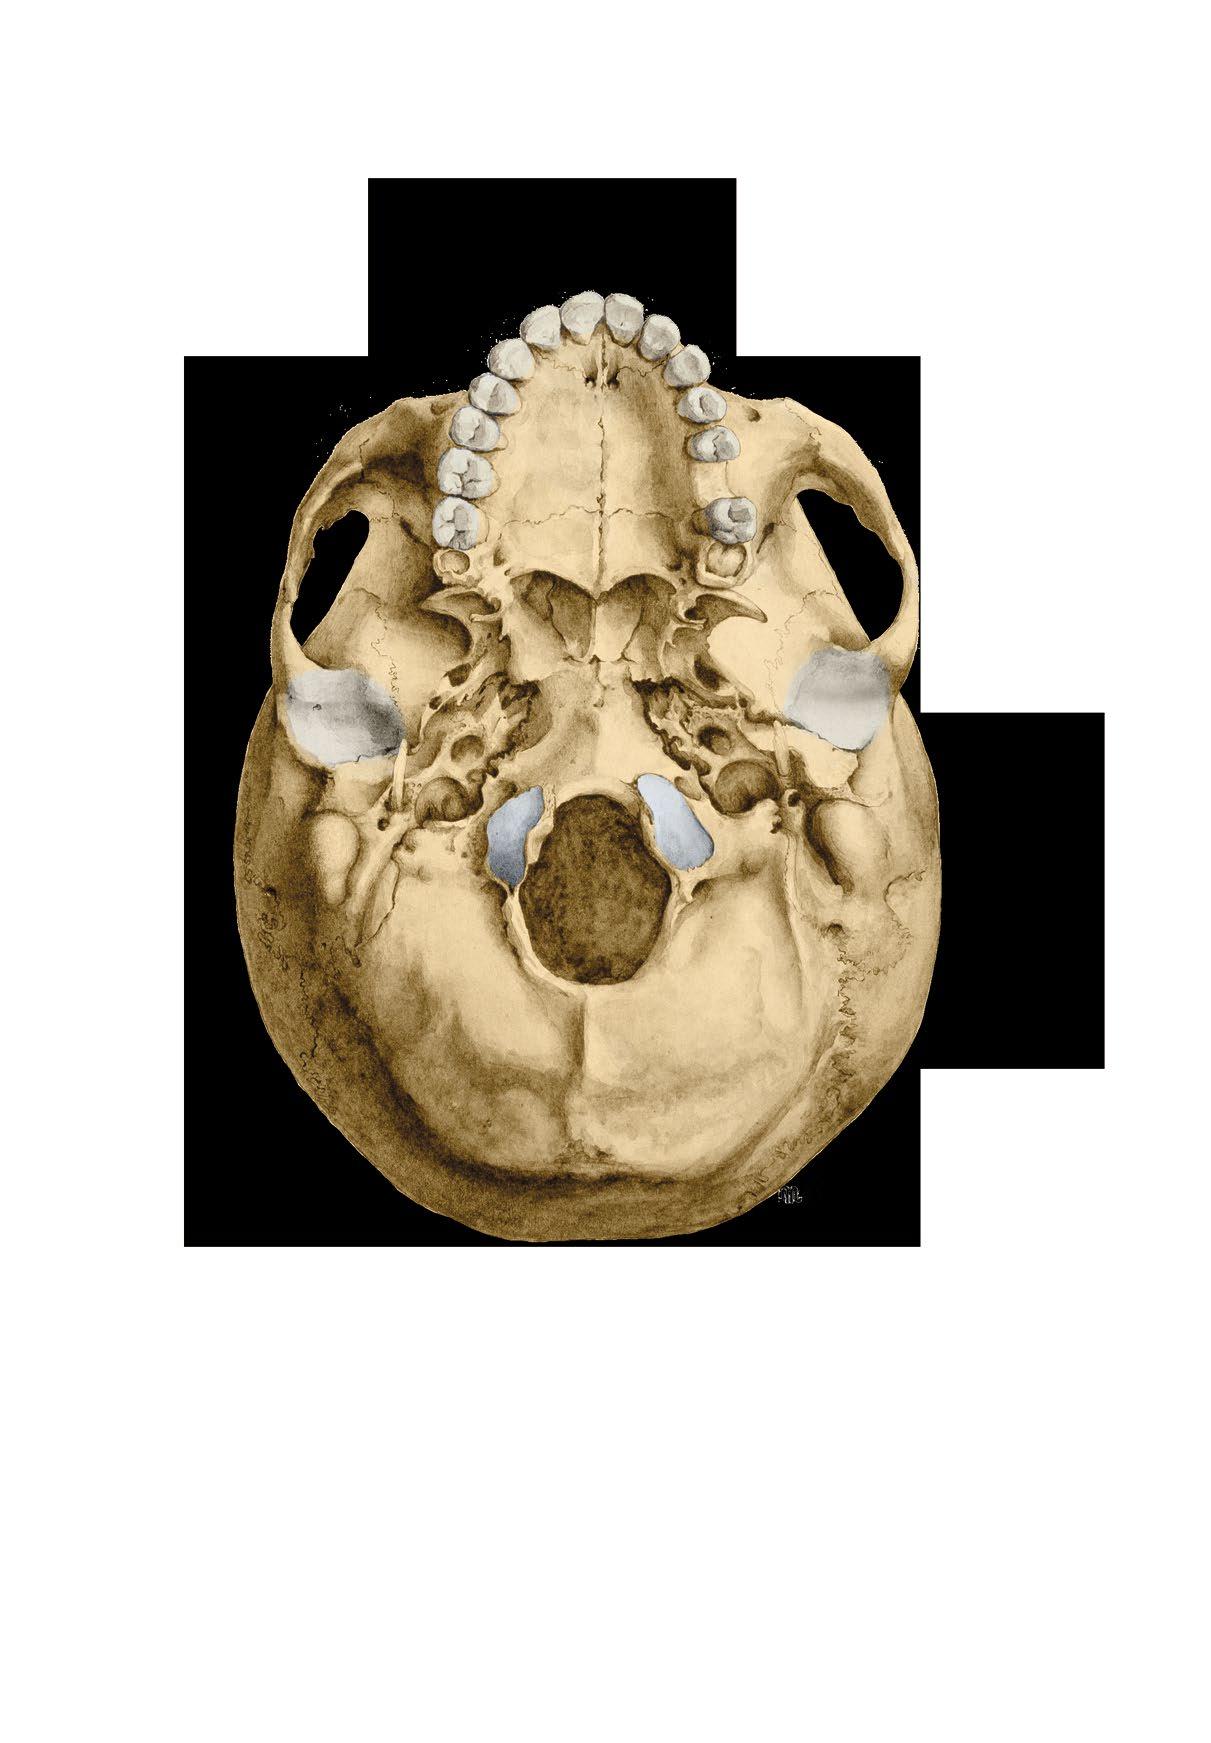

Basis cranii externa et interna

a zevní plocha base lební

b vnitřní plocha base lební

c členění vnitřní plochy base

fossa cranii posterior

External and internal base of the skull

a external surface

b internal surface c cranial fossae

Basis cranii externa, zevní plocha spodiny lebeční

External surface of the base of the skull

Basis cranii interna, vnitřní plocha spodiny lebeční

Internal surface of the base of the skull